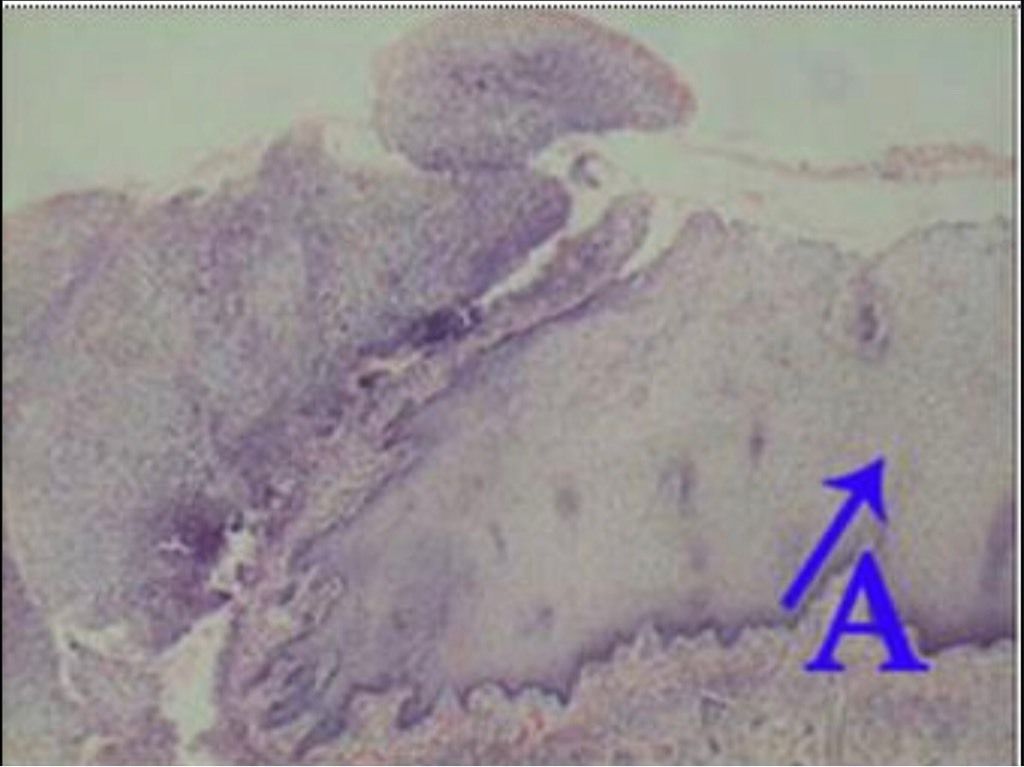

Question 1

Question

What is the correct answer at point A?

Answer

• - épithélium exocervical normal

• - membrane basale

• - cellules anormales

• - épithélium dysplasique sévère

• - massifs carcinomateux